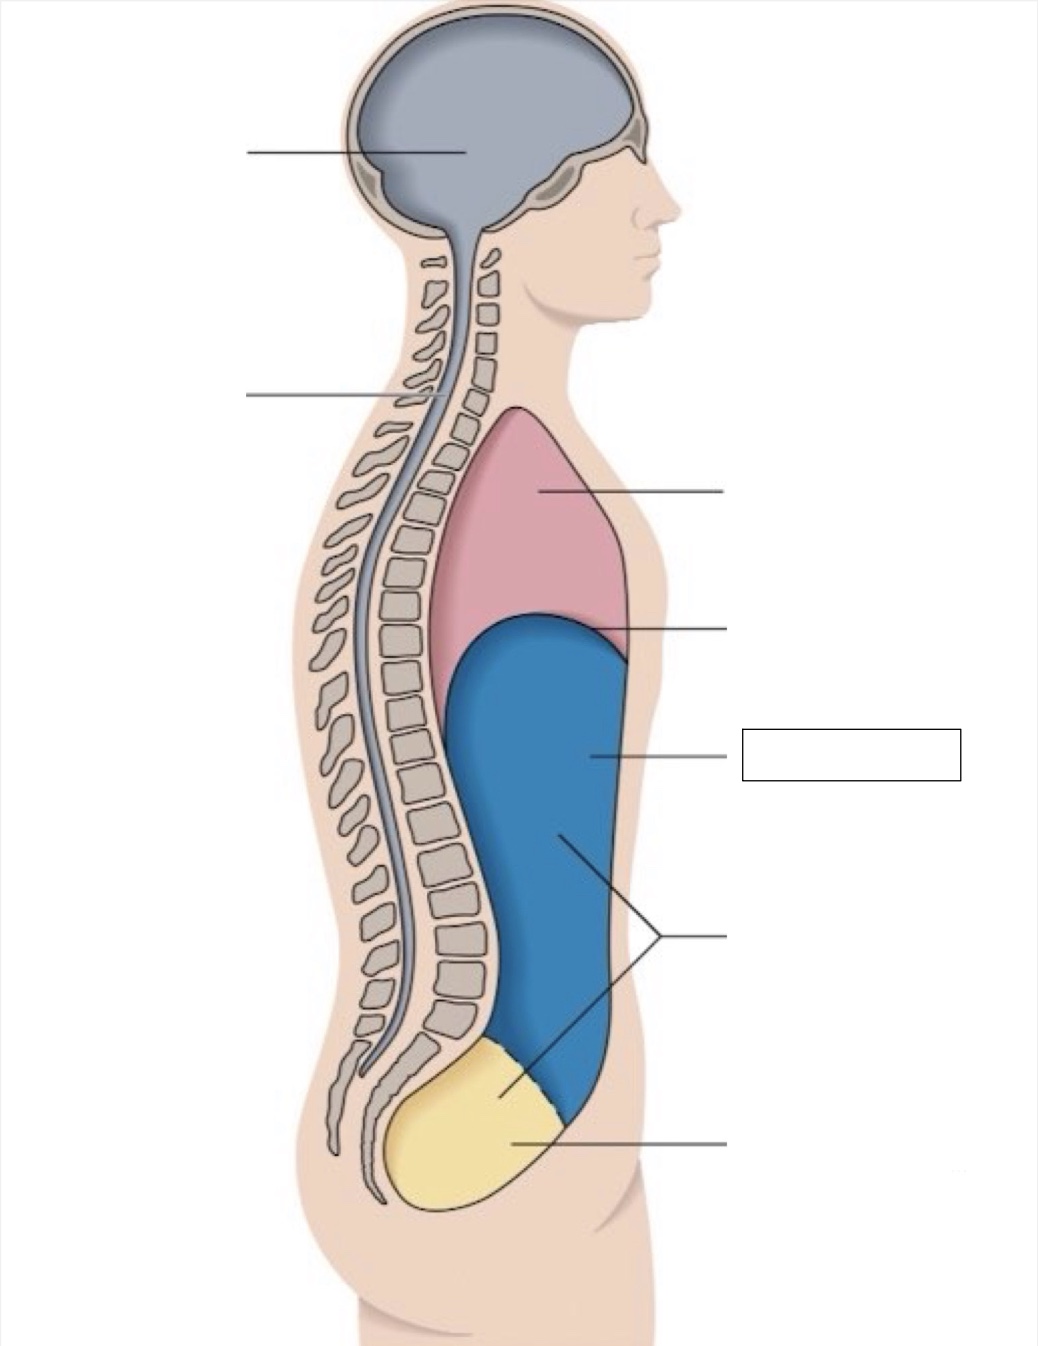

thoracic cavity

diaphragm

abdominal cavity

abdomino-pelvic cavity

pelvic cavity

spinal cavity

cranial cavity